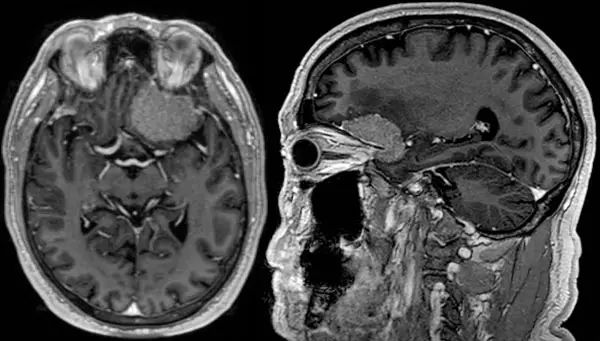

桥小脑角区脑膜瘤占全部脑膜瘤的5%~10%。这些病变需与前庭神经鞘瘤和转移瘤区别开来;影像学特点有助于鉴别诊断。下图为增强MRI扫描T1加权像,显示了经典的前庭神经鞘瘤,表现为“冰淇淋”征,呈圆柱形状,延伸至内耳道(橙色箭头)。神经鞘瘤缺乏脑膜瘤附近常见的硬脑膜增厚。脑干(绿色箭头)被肿瘤所扭曲,导致四脑室(蓝色箭头)受压,造成患者脑积水。此人表现为严重的共济失调与脑干和小脑功能障碍。